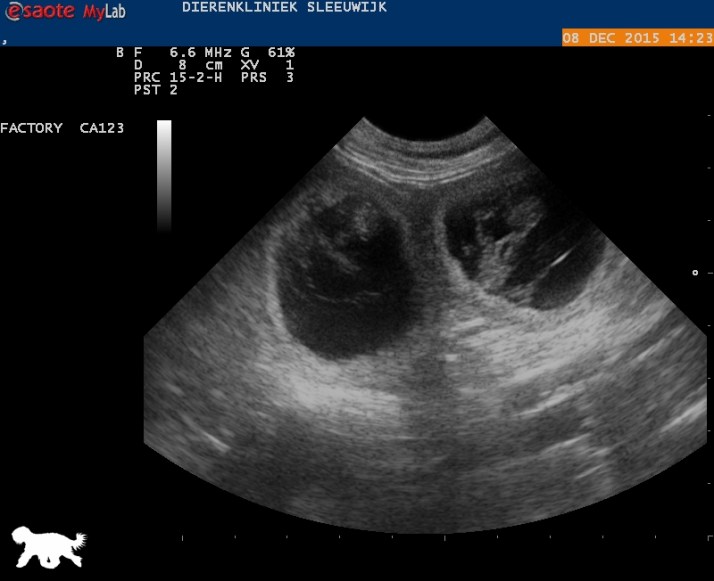

We wachten vol ongeduld tot het 9 januari is, wanneer we deze pupjes in het echt gaan zien!